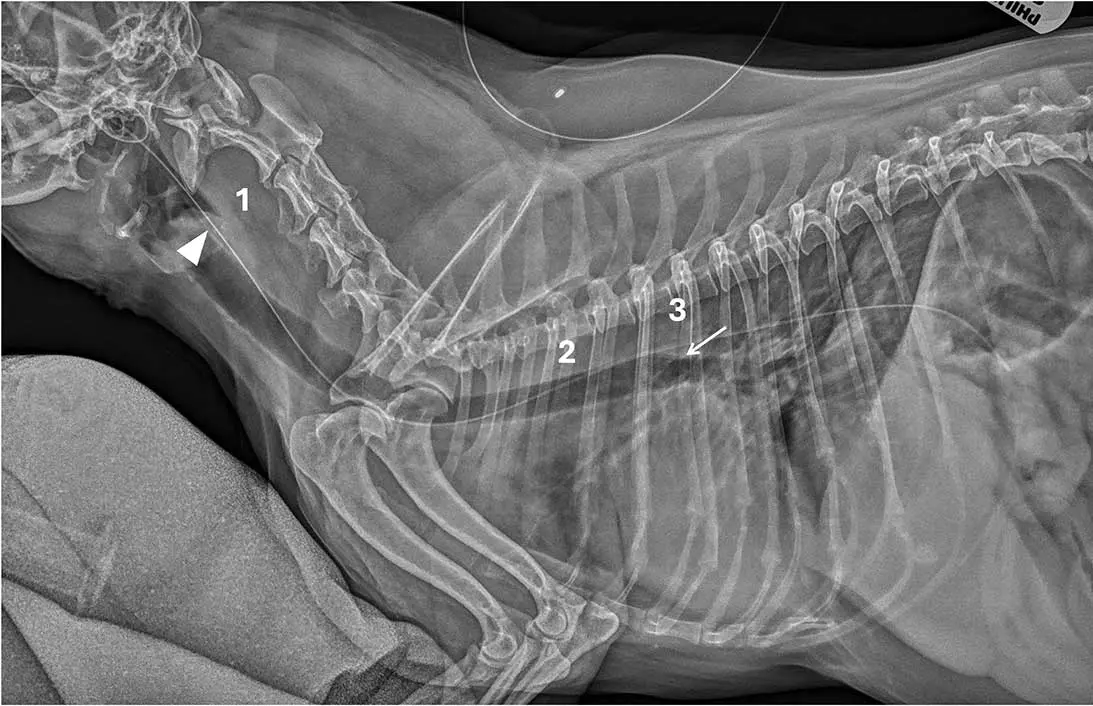

Case three

This lateral cervical and thoracic radiograph of a dog was obtained with the head rotated (Figure 3). As a result, the atlas is rotated, with the hyoid apparatus and tympanic cavities not superimposed. Therefore:

- We can not fully rely on the laryngeal landmark.

- The tube is incompletely superimposed to the tracheal lumen in the region of the carina.

- The tube is dorsal to the carina.

If the tube has not reached the carina, assessing its position in relation to the larynx may be safer than further advancing the feeding tube further. This case highlights the importance of achieving optimal patient positioning for radiography.

Interpretation. Correct oesophageal placement. At least criteria two and three were met; therefore, the tube was safely positioned for feeding.